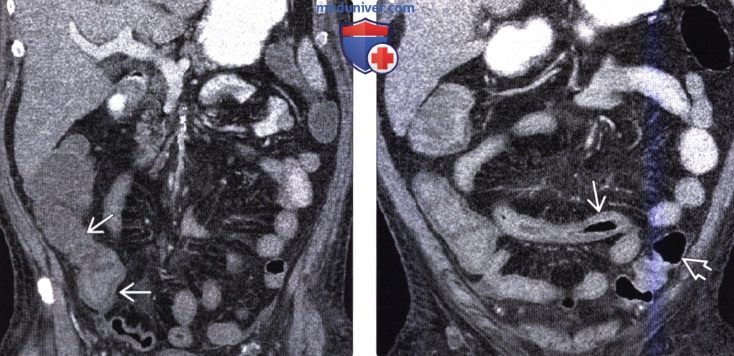

Интраренальная лоханка: рентгеновские снимки и примеры

Раздел: Фотоэссе